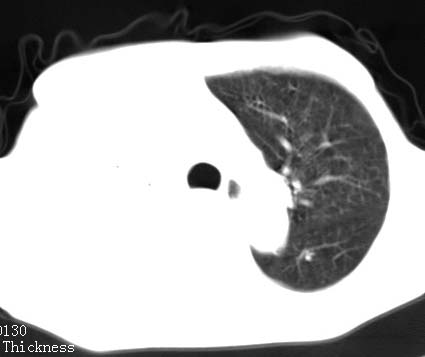

病人女 60岁 咳嗽 气促十余天,大叶性肺炎.

右肺上下叶均见 大片状密度增高影,边界清晰,其内可见支气管充气征,气管支气管通畅。纵膈略向右移位,其内无肿大淋巴结影。首先考虑炎性病变。不排除一些特异性的炎症。不知道发烧吗??wbc高吗??建议治疗后复查!!

看影响还是首先考虑炎性改变,建议实验室检查,还有要警惕炎性肺泡癌,具有的枯枝征象。

看影像还是首先考虑炎性改变,建议实验室检查,还有要警惕炎性肺泡癌,具有的枯枝征象